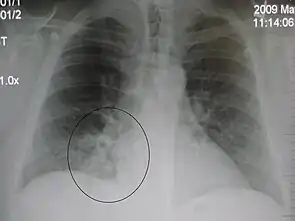

| A chest X-ray showing a very prominent wedge-shape bacterial pneumonia in the right lung | |